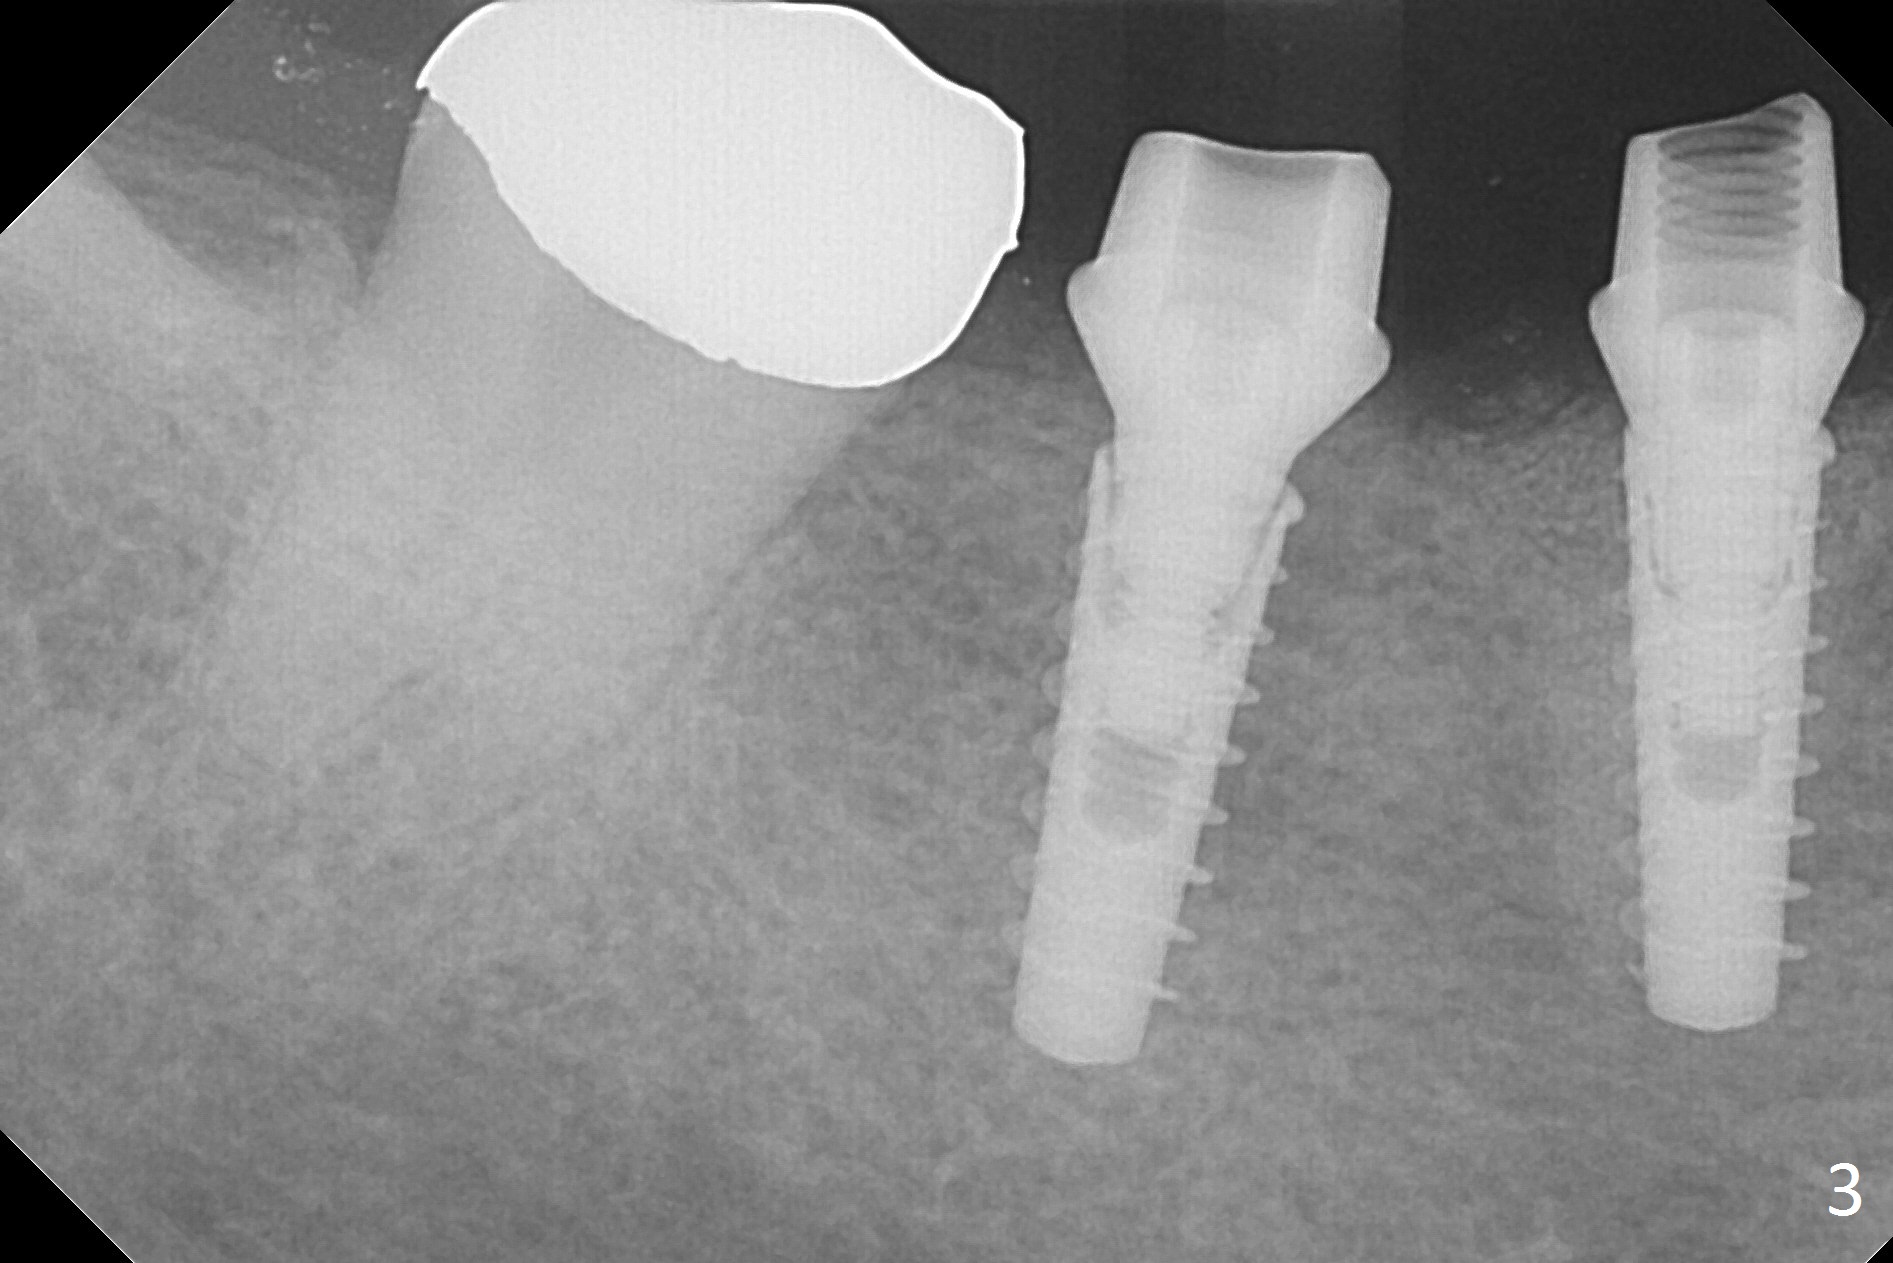

After incision, the ridge at #29 and 30 is found ~ 5 mm wide buccolingually. To place a 4x11 mm IBS implant at #30, the ridge is expanded using BEB technique (bone expansion and bending, Fig.1). It appears that the initial osteotomy at #29 is mesial (Fig.1 yellow dashed line: the distal surface of the root of the tooth #28). After moving the osteotomy distal, the final implant position at #29 (4x11 mm) is within normal limit (Fig.2). The bone at #29 seems to be not so dense that bending (using 1.6 mm drill) is not necessary (using Magic Split and Magic Expanders 3 and 3.8 mm). Later the implant at #30 (4x11 mm) is placed deeper (Fig.3). After placing bone graft around the implants/abutments and suturing, the ridge looks wider with apparent formation of the gingival bands around the abutments (Fig.4 *). Three months and a half postop, bone loss is minimal (Fig.5) and gingival bands forms around the abutments (Fig.6). Fig.7 is taken 1 month post cementation (panoramic X-ray). The patient chews normally 1 year (Fig.8) and nearly 2 years (Fig.9,10) post cementation. The crown at #31 needs recementation 2 years 7 months post #30 cementation; the incomplete seating of the abutment was noted for the first time (Fig.11). Five months later the patient is going to be retired and wants to travel abroad. After approval, the access hole was reopened; articulating paper shows under occlusion of the crown (Fig.12). Since the gap between the abutment and the implant is large, the abutment/crown complex seems to be necessary to be turned (Fig.13 curved arrow). The proximal surfaces of the crown need to be trimmed (straight lines). After turning, the crown sits down with screw tightening; the patient feels pain from the gingival cuff (Fig.14). After turning, the abutment appears to be completely seated (Fig.15). In fact the mesial and distal surfaces of the crown should have clearance from the neighboring teeth (Fig.14) so that pick-up impression is able to hold the crown/abutment complex securely (Fig.16: *). The crown is separated from the abutment after crown repair. They are seated together (loose connection) using the crown as a guide to seat the abutment. BW is taken without the crown. It appears that the abutment remains seated completely (Fig.17). The apical space is equal between #29 and 30 (Fig.17, as compared to Fig.5).